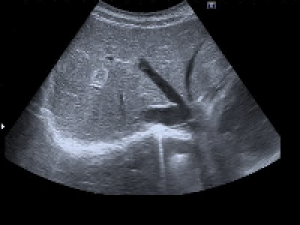

Echographie abdominale

 Restez à jeun de la veille au soir pour les examens réalisés le matin, du petit déjeuner (léger) pour les rdv l'après midi

 Ne fumez pas les 6 heures précédant l’examen,

 Prenez vos médicaments avec un peu d’eau.